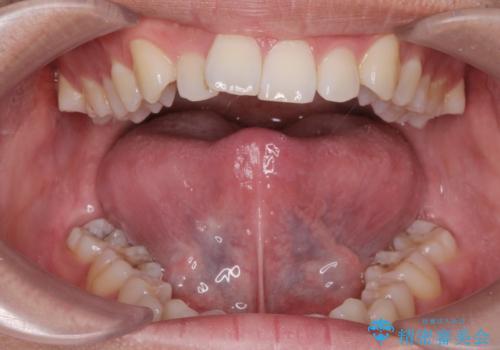

[舌小帯の形成術] 舌の動きが悪い 滑舌を改善したい!

滑舌の改善 舌小帯の形成術